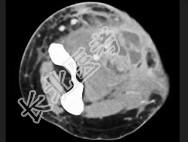

- 单项选择题男,26岁, 肘部红、肿、热、痛,疼痛呈搏动感, 结合图像,最可能的诊断是 ( )

A、脂肪瘤

B、脂肪肉瘤

C、软组织脓肿

D、血管瘤

E、淋巴管瘤